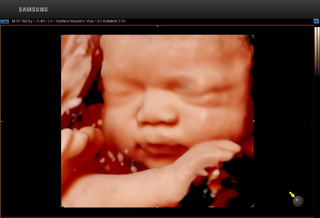

↓↓正常面部 ↓↓唇裂畸形

↓↓胎儿手部 ↓↓胎儿脚部